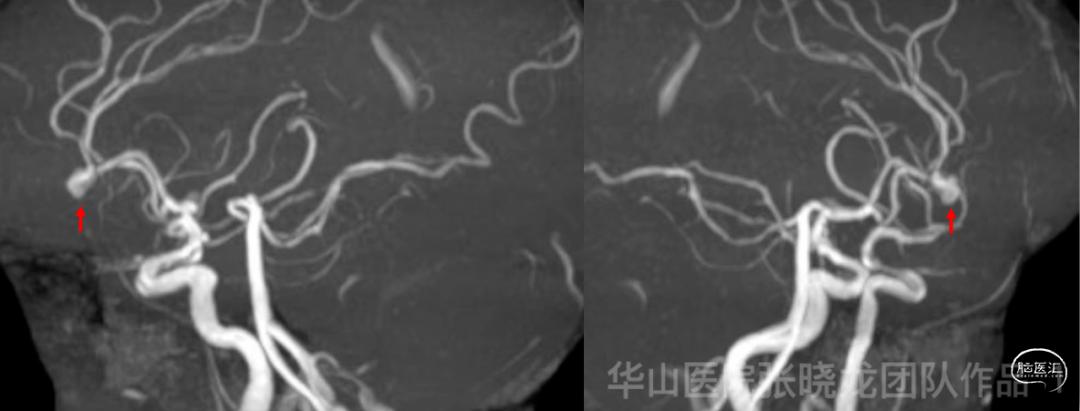

Figure 1. MRA revealed a left A2/3 bifurcation aneurysm with an irregular shape.